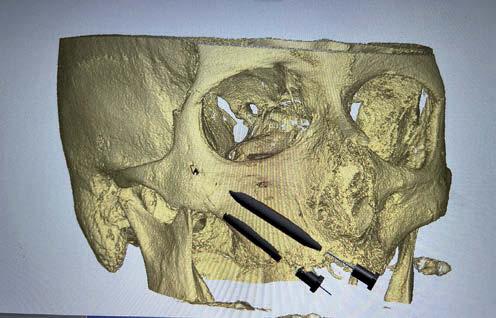

Carga inmediata en fracaso de implantes. Con implantes BLX cigomáticos Straumann Zaga Flat®️ y protocolo

Di gitalArch®️, por e l Dr. Luis Cuadrado de Vicente y cols.